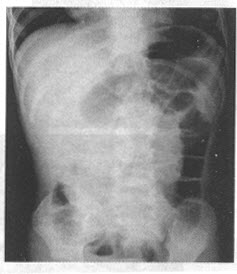

患儿,男,1岁。出现烦躁、啼哭1天,1小时前出现血便。行空气灌肠检查如图。

第1题,共3个问题

(单选题)该患者应首先考虑()

A:肠梗阻

B:肠扭转

C:肠套叠

D:坏死性小肠炎

E:肠结核

F:溃疡性结肠炎

第2题,共3个问题

(多选题)对该病的描述正确的是()

A:分原发性和继发性两种。95%以上为继发性,多为小儿

B:临床上表现为腹痛、呕吐、血便、腹部包块等

C:是婴幼儿最常见的急腹症之一。80%发生于2岁以下的小儿,女性比男性多2~3倍。多突然起病

D:病变早期应趁早手术治疗

E:典型的X线表现为空回肠换位征

F:CT表现为同心圆征

第3题,共3个问题

(单选题)对该病最有价值的影像学检查是()

A:空气或钡灌肠

B:CT

C:MRI

D:腹部平片

E:超声

F:肠镜